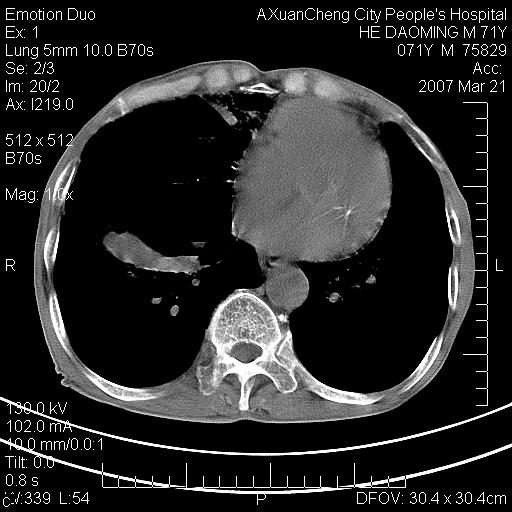

标题: CT7269:[原创] 咳嗽,咳痰,大家讨论右肺病变的部位 [打印本页]

标题: CT7269:[原创] 咳嗽,咳痰,大家讨论右肺病变的部位

1.慢支肺气肿 肺心病 肺大泡;2.叶间裂积液,前胸膜粘连

右侧相当于叶间软组织样密度ct值约50hu,请大家讨论是什么性者病变

右下肺大囊肿伴感染.肺气肿,肺大泡.

考虑:慢性支气管炎合并全小型肺气肿、肺大泡、间质纤维化、感染,右斜裂积液。

考虑慢支,肺气肿,肺大泡,间质纤维化;右侧斜裂液气胸考虑(可能因为肺大泡破裂破入斜裂所致).

考虑病变以右上中肺多发肺大泡为主并感染。请结合临床考虑慢支肺气肿,肺心病。

1双肺慢性支气管炎并全小叶型肺气肿肺大泡2间质性纤维化3右侧斜裂积液

考虑:慢性支气管炎合并右侧全小型肺气肿、肺大泡并感染、双肺间质纤维化,右斜裂积液。

考虑:慢性支气管炎合并右侧全小型肺气肿、肺大泡并感染、双肺间质纤维化,右斜裂积液。右侧斜裂液气胸考虑(可能因为肺大泡破裂破入斜裂所致).